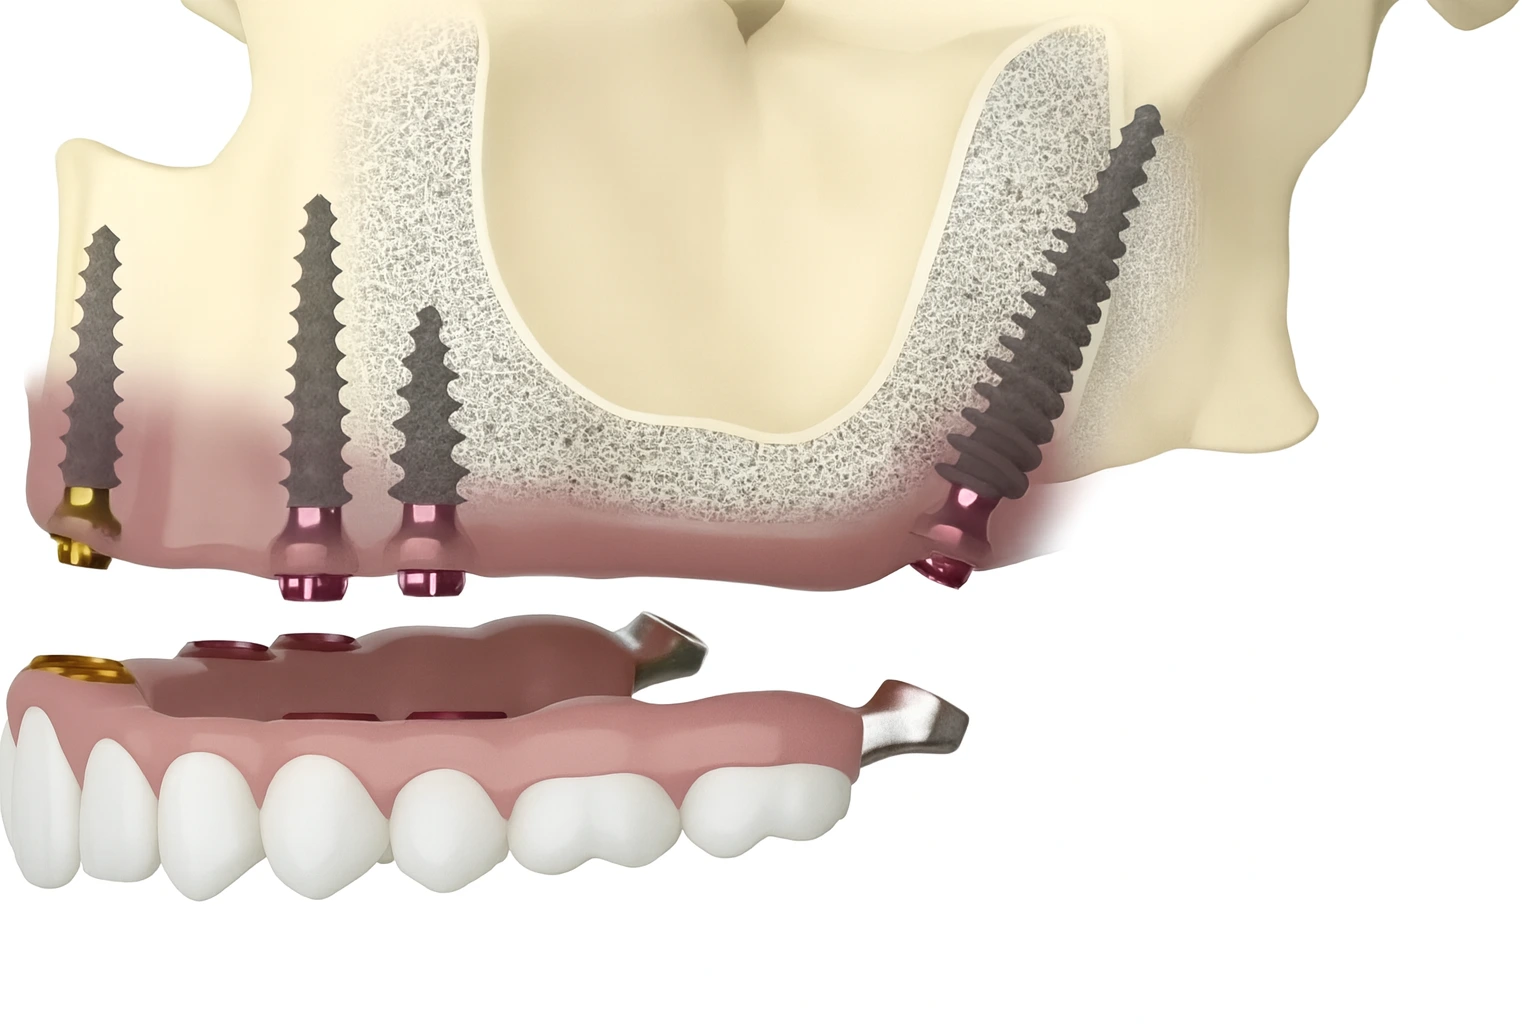

For advanced bone loss. Basal implants anchor in dense cortical bone for strong stability. Suitable cases may get fixed teeth faster with fewer surgical steps.

Many patients think they must do bone grafting first. Some cases can avoid that with graftless implants. You get a safety first plan, comfort focused treatment, and a clear timeline. Every case is different, so we confirm suitability with a 3D scan before treatment.

Your safety comes first. We confirm your suitability with a 3D scan and medical review. We also explain possible side effects like temporary swelling or soreness, and how we manage them.